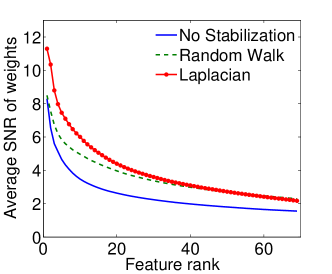

|

|

| (a) Cumulative, | (b) Stagewise (Shared), |

|

|

| (c) Stagewise (Separate), | (d) Stagewise (Separate), |

We now examine the models stability against data sampling and evaluate the stabilizing property of the proposed method (Sec. 6.2). For each fold, we generated samples, each of which was drawn randomly from % of training data. Each example resulted in a model, and the feature weights were recorded and finally the results of all folds – models – were combined. Figs. 5(a–d) show the indices (Eq. (5)) as functions of the rank list size , for all ordinal classifiers. The instability is clearly an issue – the average selected probability drops as more features are included. Using both the Laplacian and random walk regularization methods (Eqs. (9,10)), the improvement in stability is evidenced in all settings. The instability and stabilizing effect were similarly obtained with the indices (Figs. 6(a–d)).